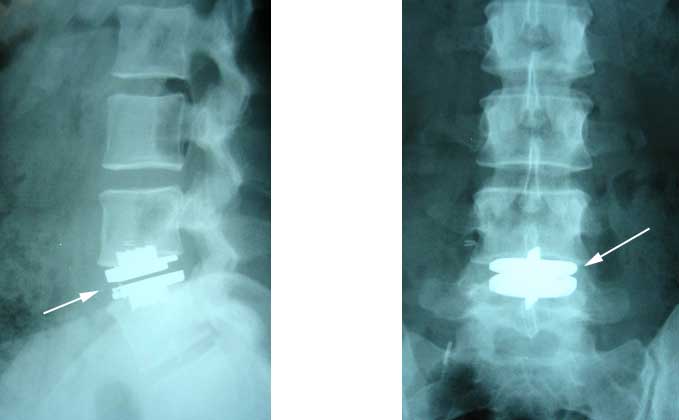

Disc Replacement

Disc replacements have now been approved for use in the United States. The replacement technology has gone through multiple revisions since its infancy in Europe. Disc replacements are ideal for the younger patient who has degenerative disc disease causing low back pain.